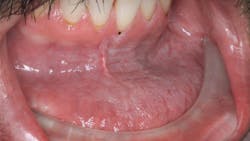

Patient: 27-year-old male

- Chief complaint: upper right tooth, third from the back, was bothering the patient progressively over the last few months

- Patient has slightly elevated blood pressure and is a chronic tobacco user

- Rough, corrugated-cardboard-like tissue in large area of lower left vestibule

- Patient is aware of the risks associated with tobacco